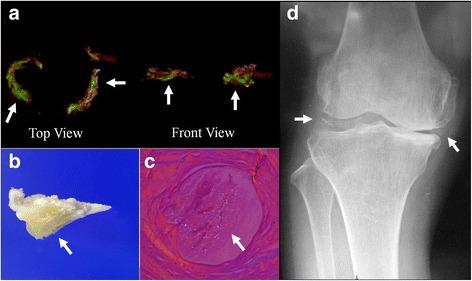

CPPD crystals in synovial fluid were observed in 9 (36%) patients. The sensitivity and specificity of DECT in the detection of CPPD crystals, against microscopic identification, were 77.8 and 93.8%, respectively. The sensitivity and specificity of conventional radiography in the detection of CPPD crystals were 44.4 and 100%, respectively. DECT was able to detect the area where CPPD crystals were deposited in the meniscus.

DECT provides good diagnostic sensitivity and specificity for detection of CPPD crystals in knee meniscus as well as spatial information about CPPD crystals. DECT is currently a research tool, but we believe that DECT can be a useful instrument to diagnose CPPD deposition disease, especially for the regions where aspiration is difficult to be performed such as pubic symphysis, atlantoaxial joint, interphalangeal joint.

9例(36%)患者的滑膜液中观察到CPPD晶体。与显微镜鉴定相比,DECT检测CPPD晶体的敏感性和特异性分别为77.8%和93.8%。传统X线摄影检测CPPD晶体的敏感性和特异性分别为44.4%和100%。DECT能够检测到半月板中CPPD晶体沉积的区域。

DECT在检测膝关节半月板中CPPD晶体方面具有良好的诊断敏感性和特异性,以及关于CPPD晶体的空间信息。DECT目前是一种研究工具,但我们认为DECT可成为诊断CPPD沉积病的有用仪器,尤其是对于耻骨联合、寰枢关节、指间关节等难以进行抽吸的部位。